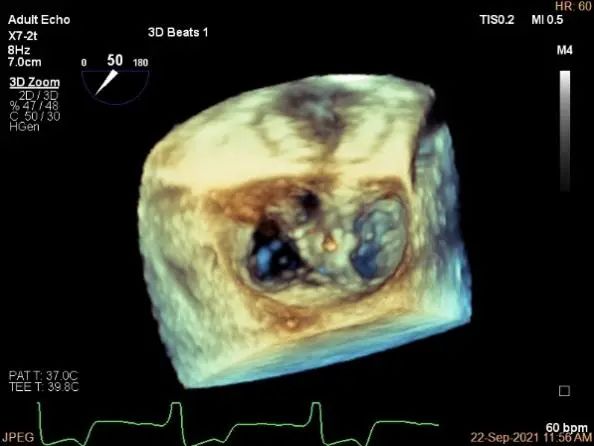

夹子夹闭后,未见明确残余分流

3d确认夹子位置在P1区

3d-color确认残余分流情况

评估二尖瓣瓣口平均跨瓣压差:1mmHg

肺静脉血流频谱恢复正常